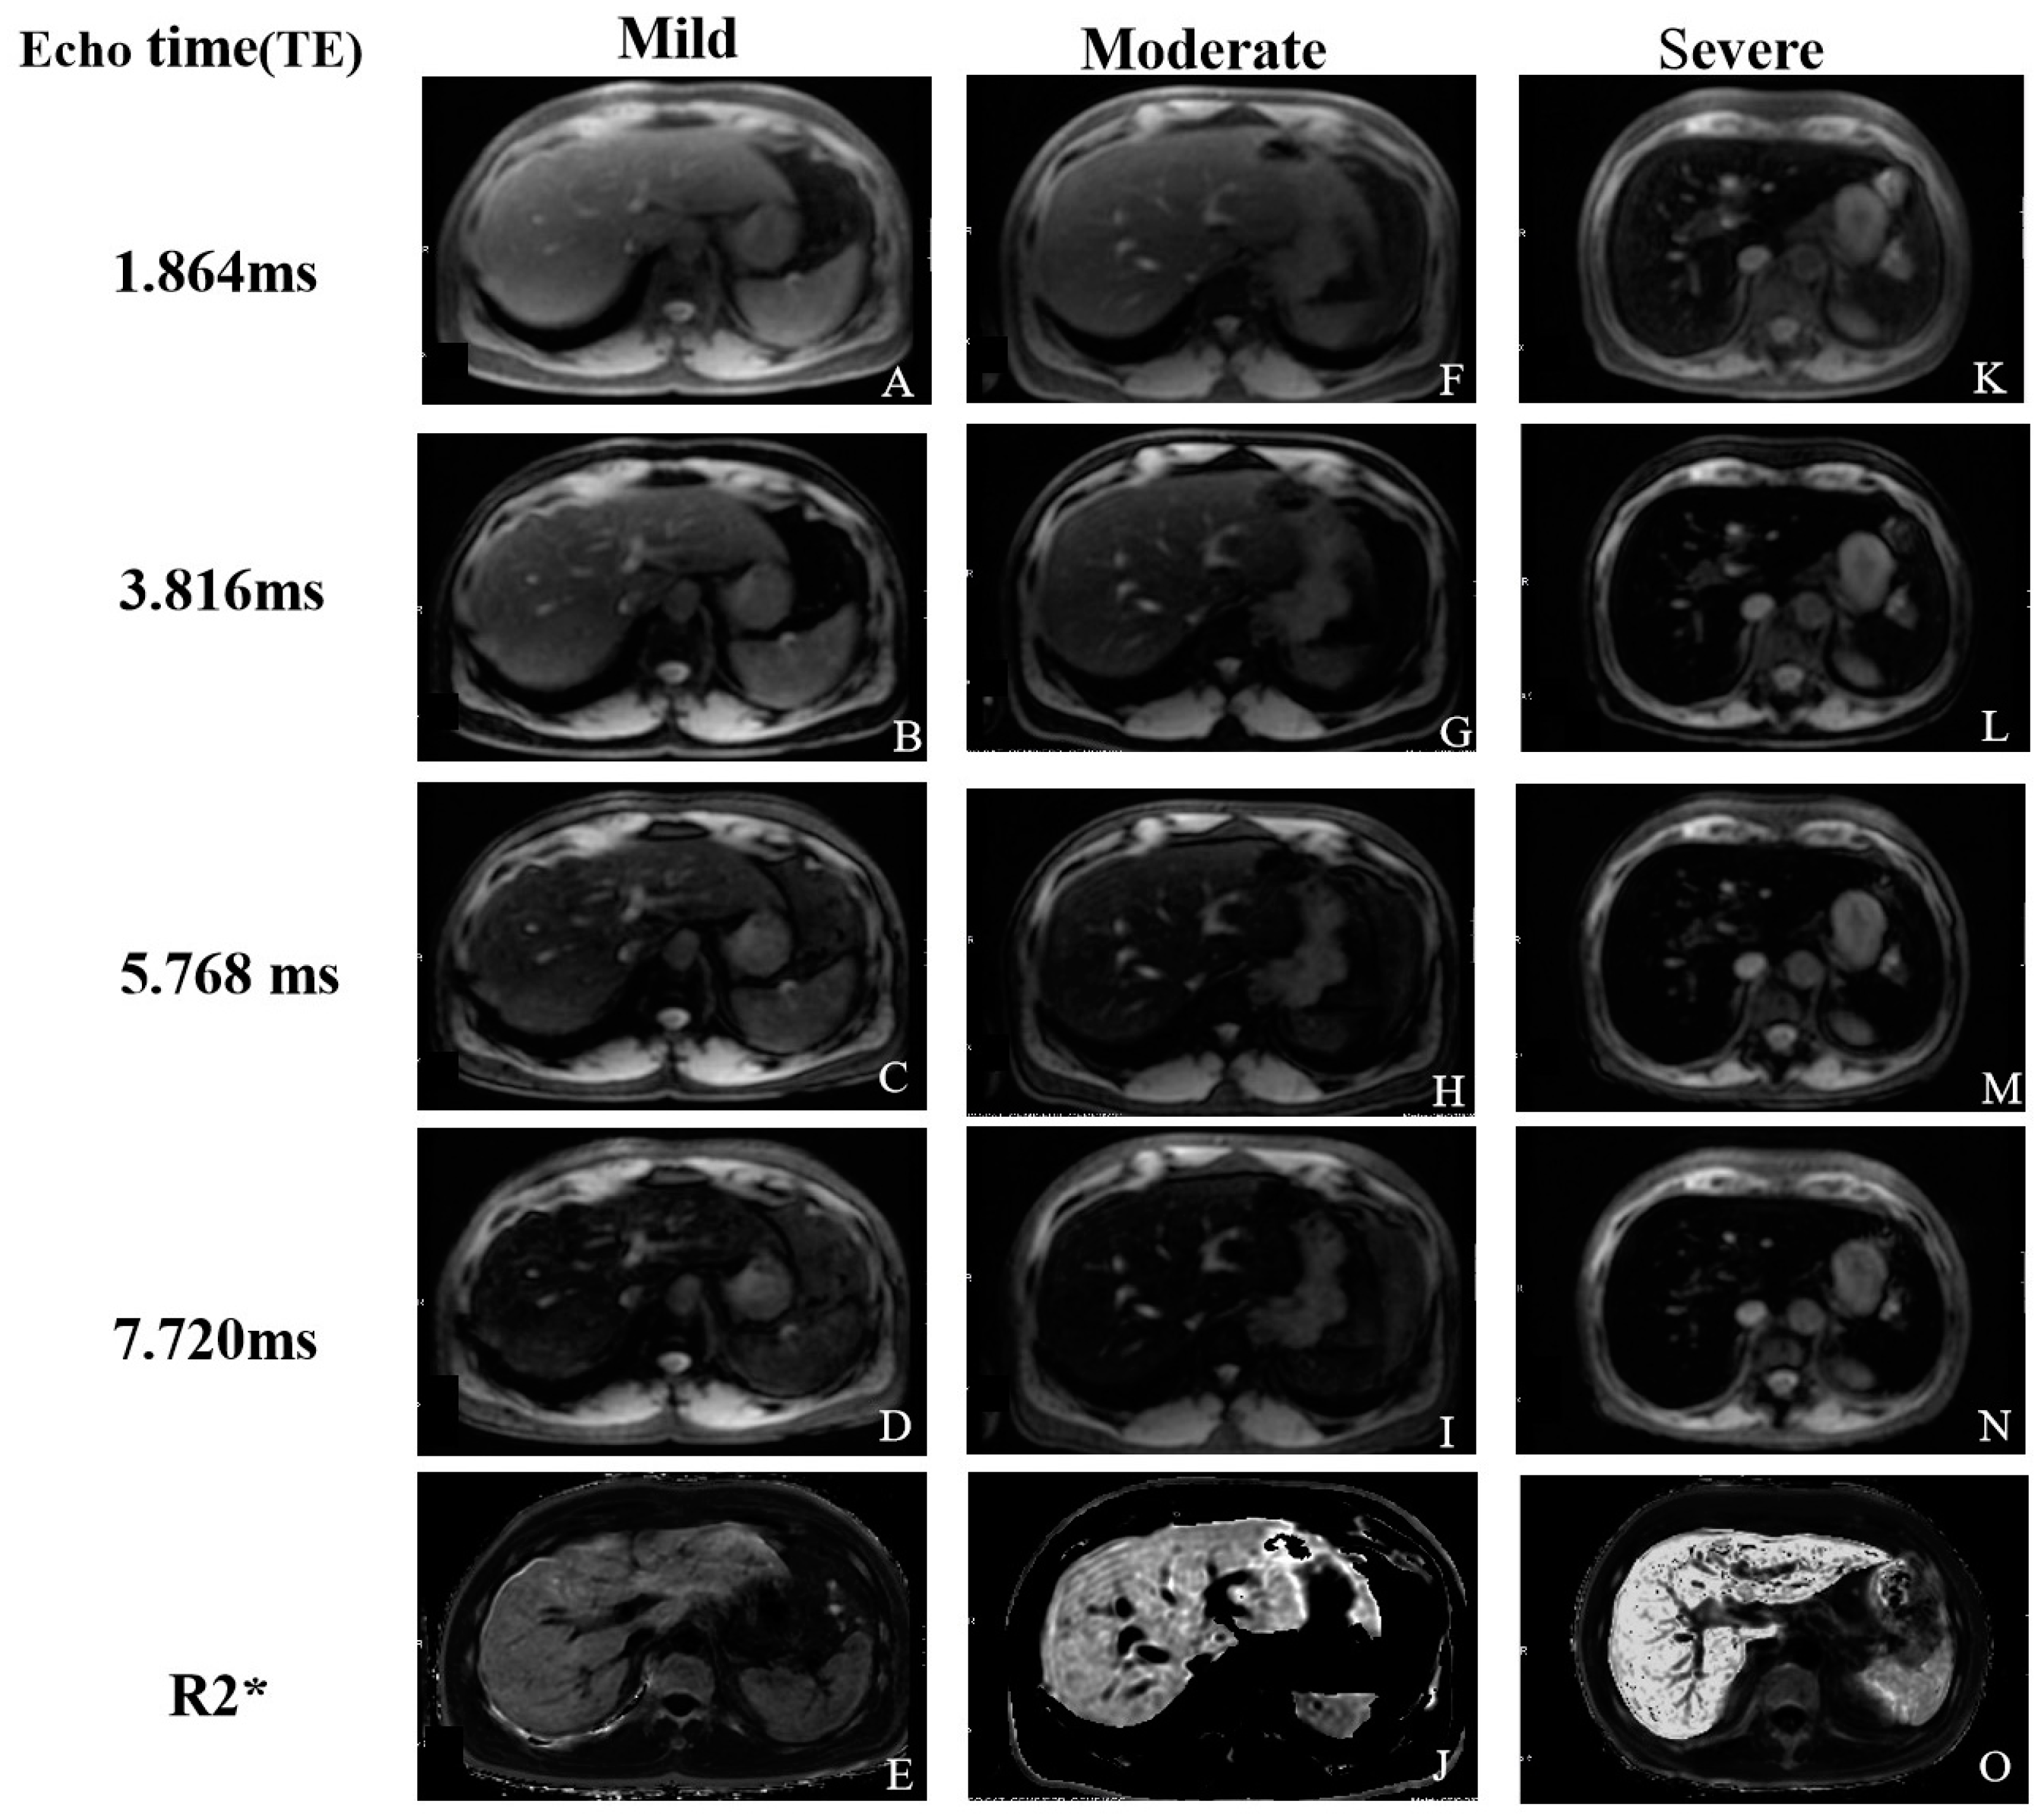

2.2.3. T2* and R2* Relaxometry